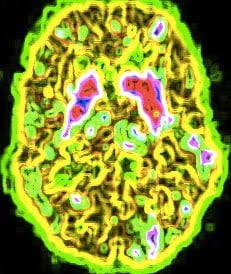

A study in JAMA Psychiatry (The Brain on Porn) enrolled 64 German men who regularly viewed pornography and took a look at their brains using scanning techniques. They found a significant negative association between hours of pornography per week and the volume of grey matter in parts of the brain. They also found other changes and speculated that the intense stimulation of the reward system may have caused the changes. Of course the changes could have been there before the porn use, making the porn more rewarding when they first started to view it. The authors thought the former theory to be more likely.